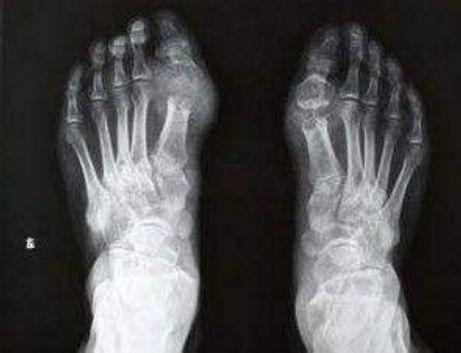

大家好!我是你们最贴心的“育儿张医师”,拥有健康的身体,应该从一点一滴做起!如:不偏食、不厌食、不挑食!并且要做到每天体育锻炼!还有多喝水,多吃水果。健康来自健康的生活习惯,关注张医师,每天为大家推荐健康小妙方。现在随着人们的生活越来越好、享受生活的人越来越多,却忽视了健康的问题,不少人都患上了痛风的毛病,那么除了要遵从医嘱定时定量用药、配合治疗之外,饮食上还有什么可以帮助人体排尿酸的呢?今天就给大家介绍几种碱性水果,每一种都是排尿酸的高手。